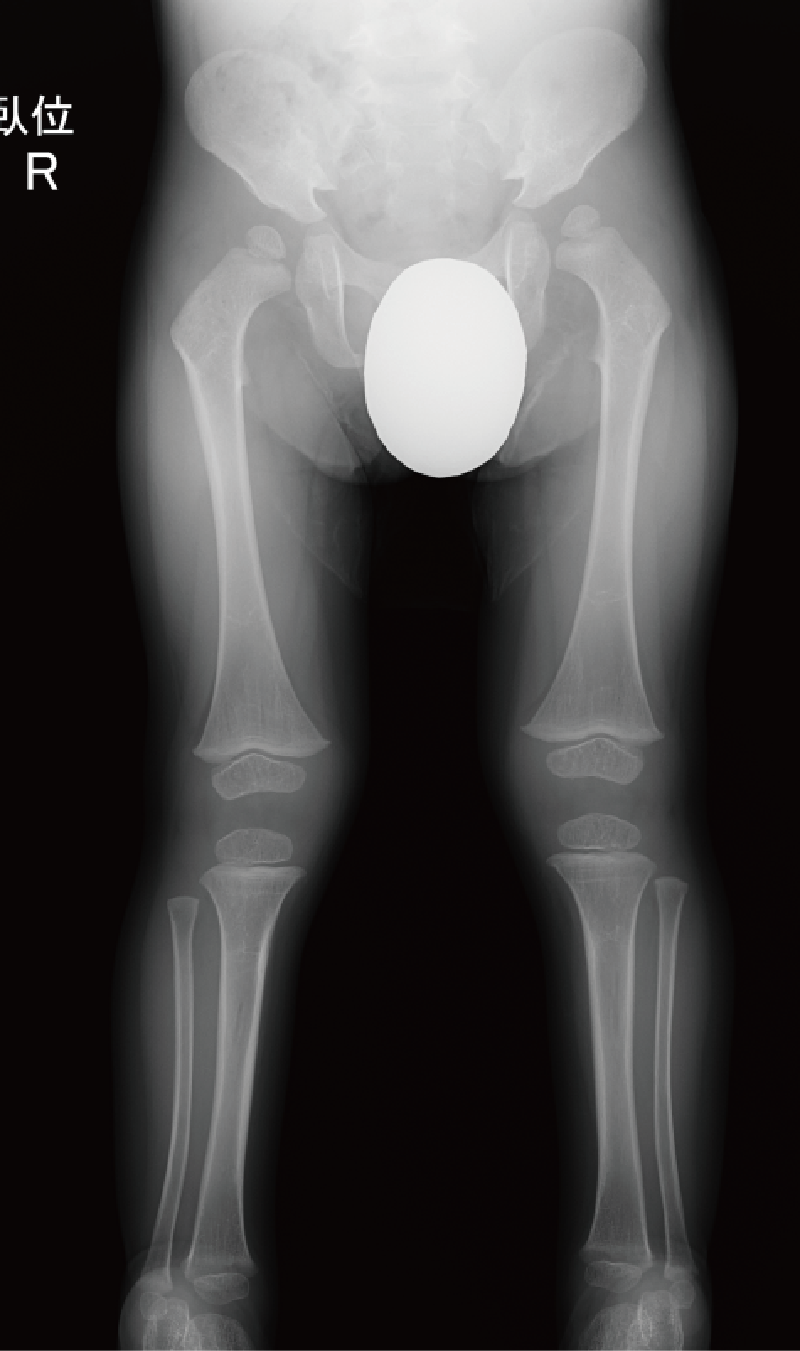

A. 背面像(6歳、女):内反膝を伴った体幹短縮型低身長。

B. 両下肢正面像(6歳、女):著明な内反膝および、大腿骨頭骨端核や膝周囲の骨端核の骨化遅延を認める。